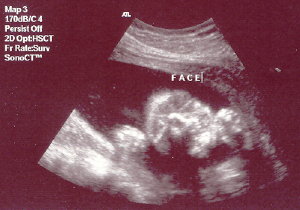

My Latest Ultrasound.... I just had an ultrasound on Tuesday, July 11th. I was so excited that all ate that morning was a Chewy Granola Bar. The ultrasound was at 1:00 p.m., so during the ultrasound, I almost fainted. The room started to go black. My body temperature felt like it was dropping, BUT I broke out in a sweat, and the sound drained from the room. All I could do was grab Duane's hand, as if holding on for my dear life. Go figure. Can anybody say "low blood sugar." Oh well. My husband gave me the whole lecture on how breakfast is the most important meal of the day, etc.... So you can all save your preaching for another day, thank you very much. Other than that, the whole day was so exciting! WE'RE HAVING A BOY! Here are some ultrasound pictures for you. Sorry they're not that clear but it's better than nothing, right? Enjoy...